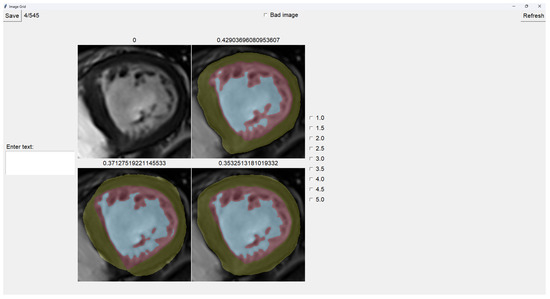

The program presents four images on a grid, as shown in Figure 5. The raw image is presented in the top-left corner, while the other three images are segmentations obtained differently. These three images are randomly placed in each iteration to ensure that this is a blind test.

On top of each image, we show the percentage of image trabeculation for the given segmentation (Equation (1)).

Again, we use a muted color scheme to make the colors distinguishable for colorblind people. The External Layer is olive, the Internal Cavity is cyan, and the Trabecular Zone is rose.

To select an image, you have to left-click on the image, and then a green box appears around the selected image (see Figure 6). On the right, we can choose a mark of 1–5, indicating how good the image is. Table 1 shows the subjective evaluation scale proposed in [23]. Finally, we can save it, which automatically brings up the next batch.

In addition, we can give feedback in the textbox on the left. We can also indicate whether the quality of the image is bad by selecting the checkbox at the center top.

The three images presented (see Figure 5 and Figure 6) are obtained using the following methods:

• Original targets: QLVTHC output [11].

• Blob-selection method: We compare the cross-validation method (Section 2.1) for improving images to the QLVTHC method on the image fixer. We improve the images only by choosing the best blobs based on their differences.

• Manually fixed method: We manually fix 100 images by coloring on the image fixer (left-click). We perform the cross-validation method on these 100 fixed images and continue manually fixing 400 more images using these outputs as a new base.